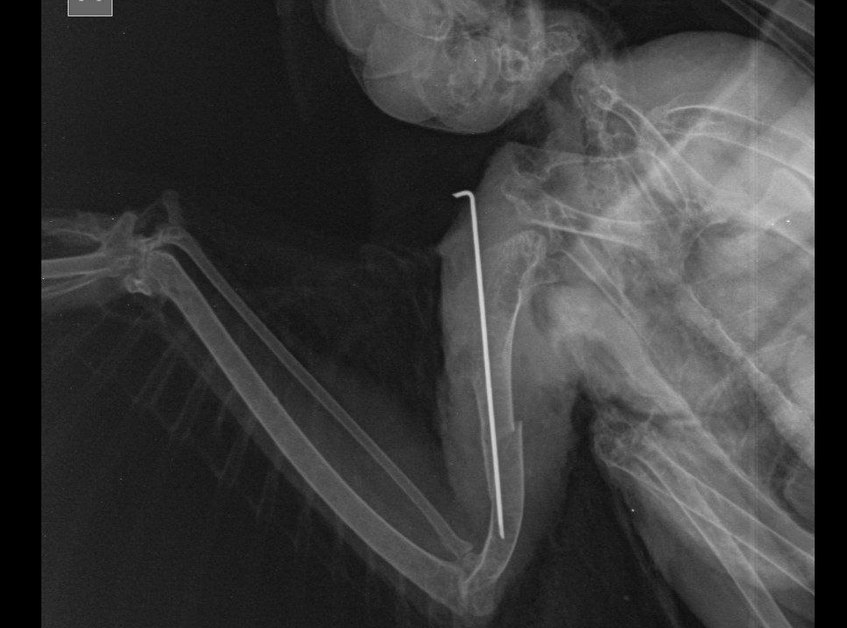

– Мы сделали рентгеновский снимок, на котором виден открытый перелом правого крыла со смещением мягких тканей. Поэтому пришлось провести остеосинтез кости. Говоря простым языком, в крыло птице была введена осевая спица, которая поможет тканям срастаться, – рассказывает ветврач. Павел Жульпа поясняет: птицы очень тяжело переносят наркоз, однако в данном случае операция прошла успешно. Ястреб пришел в себя и уже несколько дней находится в стационаре клиники под круглосуточным наблюдением врачей.

– Ястреб должен быть ограничен в движении до тех пор, пока кости не срастутся. На это может уйти от нескольких недель до двух месяцев. А когда наступит пора, Сапсанчика вновь привезут в Лиду, чтобы снять с крыла спицы, – поясняют в Центре спасения животных.От редакции. Пока материал готовился в печать, ястреб уехал к себе на родину в Червенский район. Будем надеяться, что перепелятник не только оправится от травмы, но и сможет вернуться в дикую природу.